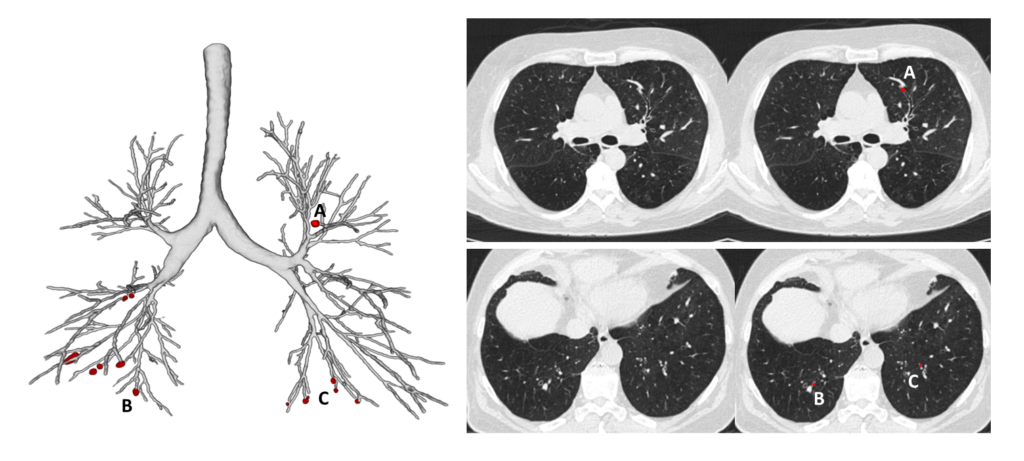

With the precision and robustness that deep learning technology brings to the table, we can recognize and precisely quantify details that could not be detected before. We are now able to look deep into the entire bronchial tree, and measure all relevant airway dimensions up to the smallest bronchi. This allows us to obtain objective, accurate, and sensitive information of all the bronchi visible in the scan in a matter of minutes. In addition, AI algorithms are much faster and more precise in detecting, localizing and counting mucus plugs (Figure 1).